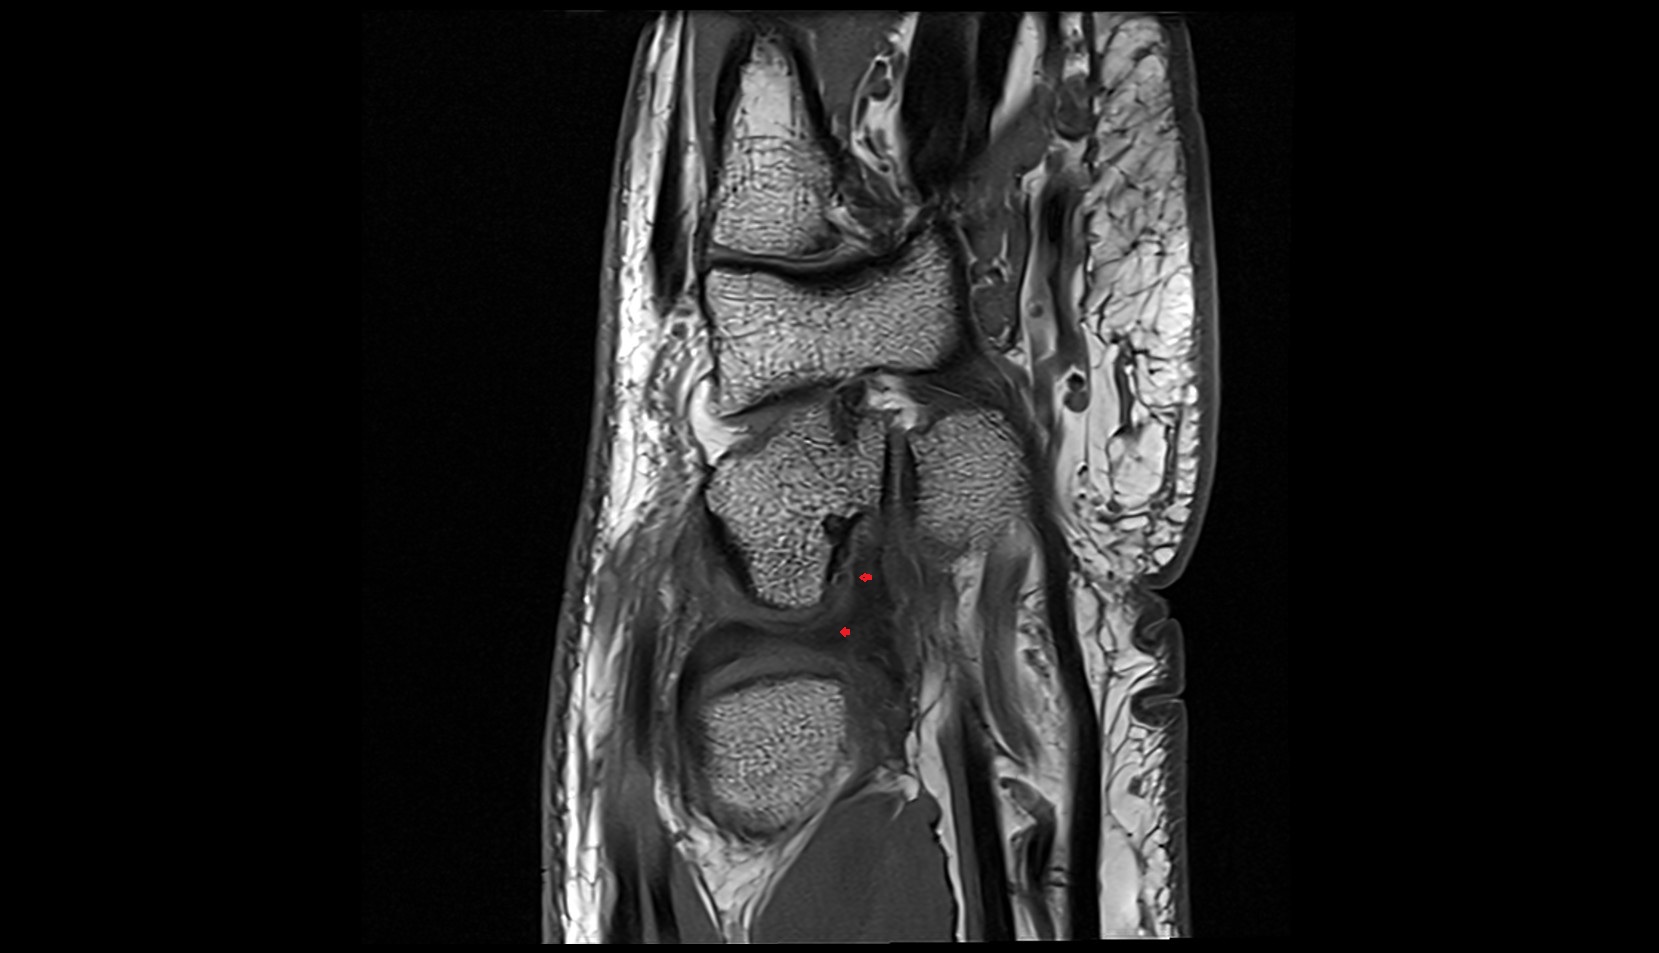

- Anterior cruciate ligament

- Posterior cruciate ligament